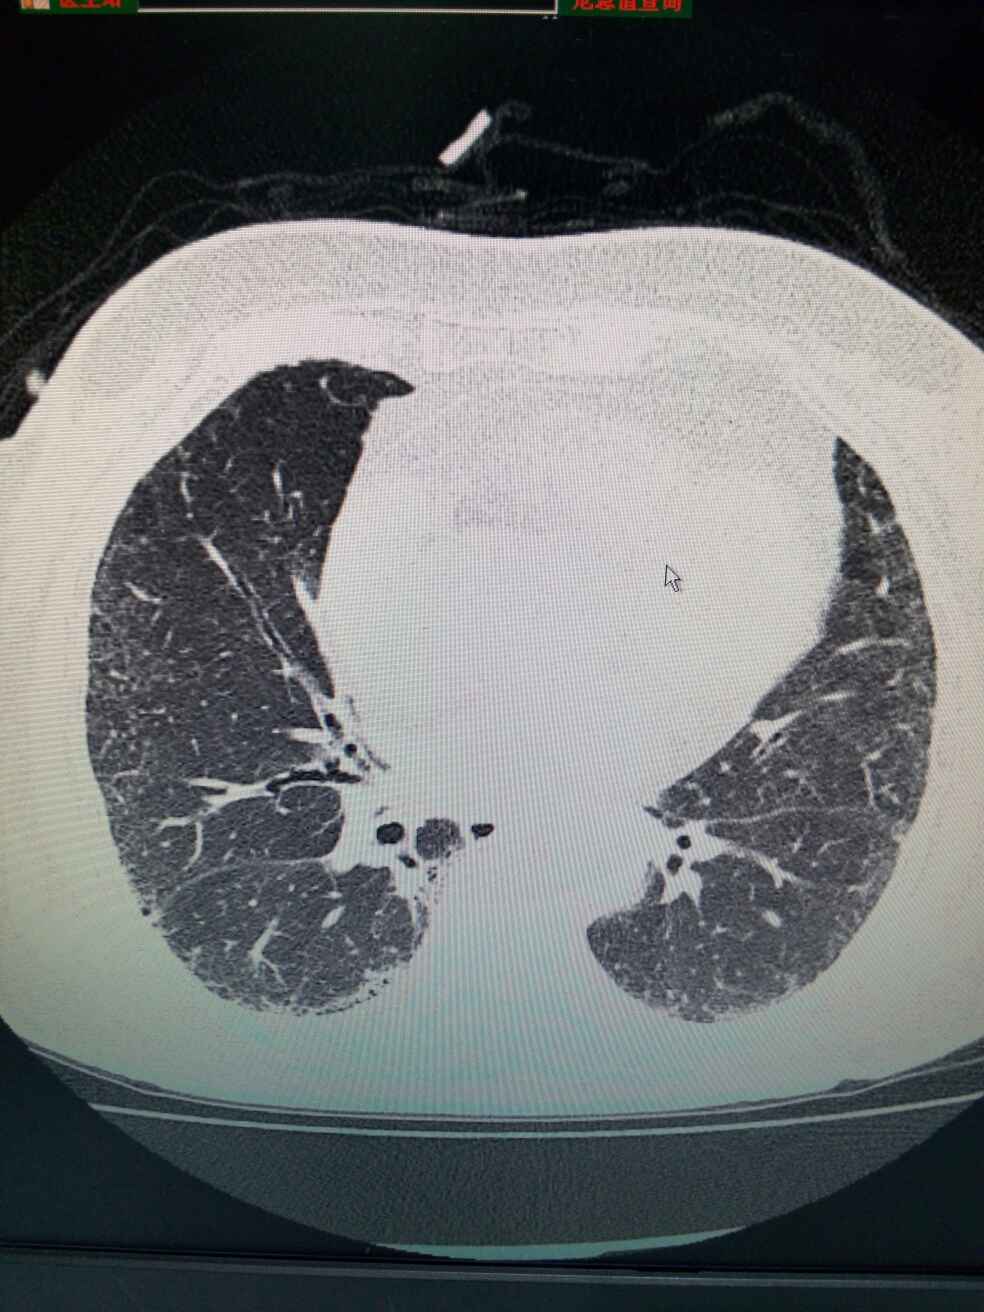

双肺间质性病变,纵膈多发小淋巴结。